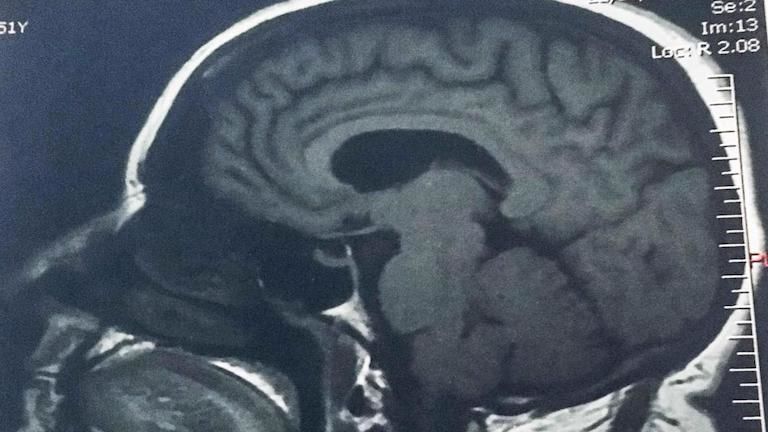

Csodálatos gyógyulás: nyomtalanul eltűnt a kislány agyából a tumor

A menopauzára fogták a fejfájást, kiderült, hogy agytumor

Tojásnyi tumort távolítottak el az agyából – végig ébren volt

Agydaganatot állapítottak meg az Édes élet egyik szereplőjénél